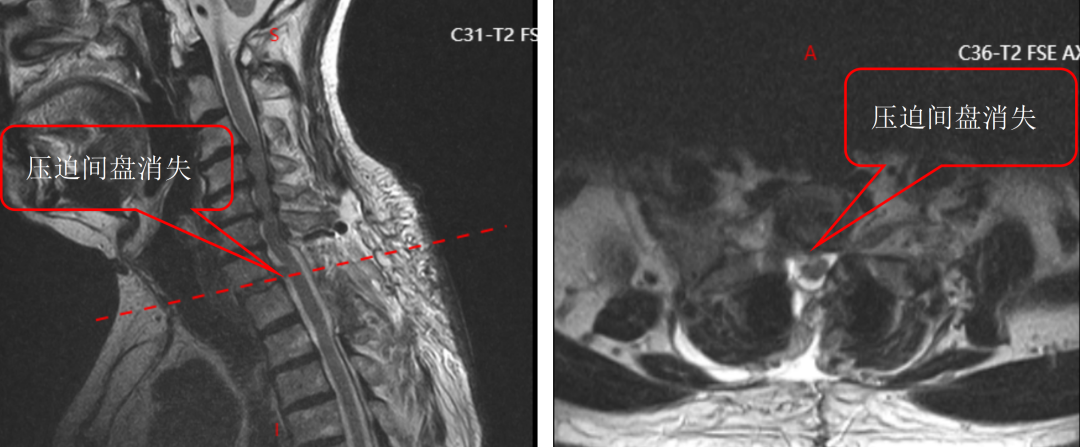

面对这一特殊情况,吴静晔主任没有急于下结论,而是为患者进行了细致全面的检查,最终精准诊断为脊髓型颈椎病。而进一步检查显示,患者存在C3-T1多节段狭窄,病情复杂且手术节段较多,这无疑给治疗带来了巨大挑战。

为最大程度降低手术损伤,保障手术安全,吴静晔主任、王肖虎主任带领团队反复研讨,最终制定了更贴合患者情况的手术方案——C7-T2节段全椎板切除减压、髓核摘除、椎弓根螺钉内固定术。

术后复查结果也令人振奋,患者螺钉位置良好,椎管减压彻底,原本麻木、无力的双下肢症状明显改善,行走能力逐步恢复。看着老先生摆脱病痛困扰,脸上重新露出笑容,医护人员也倍感欣慰。